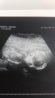

No to nieźle dziewczyny.. W 15tc miałam mieć synka, ciuszki pokupowane a tu psikus ! Wczoraj Usg połówkowe a tu dziewczynka ! :D Pójdę jeszcze za 2 tygodnie na Usg 4d, ale no po prostu szok ! Każdy obstawiał chłopca..a tu w tym roku urodzi się 2 babka(Moja bratowa jeszcze nie zna płci więc możliwe że będą trzy hahah :) )

Załączniki

• aaaa.jpg

aaaa.jpg

28,2 KB · Wyświetleń: 100